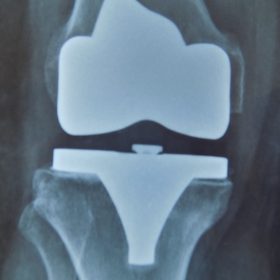

Παρόλα αυτά στην πλειονότητα των περιπτώσεων, με την πάροδο του χρόνου οι παραπάνω τρόποι αντιμετώπισης καθίστανται αναποτελεσματικοί. Η ένταση του πόνου και ο αντίκτυπος στην καθημερινότητα γίνονται αφόρητα.

Σε αυτό το σημείο η Αρθροπλαστική Γονάτου αποτελεί μονόδρομο.